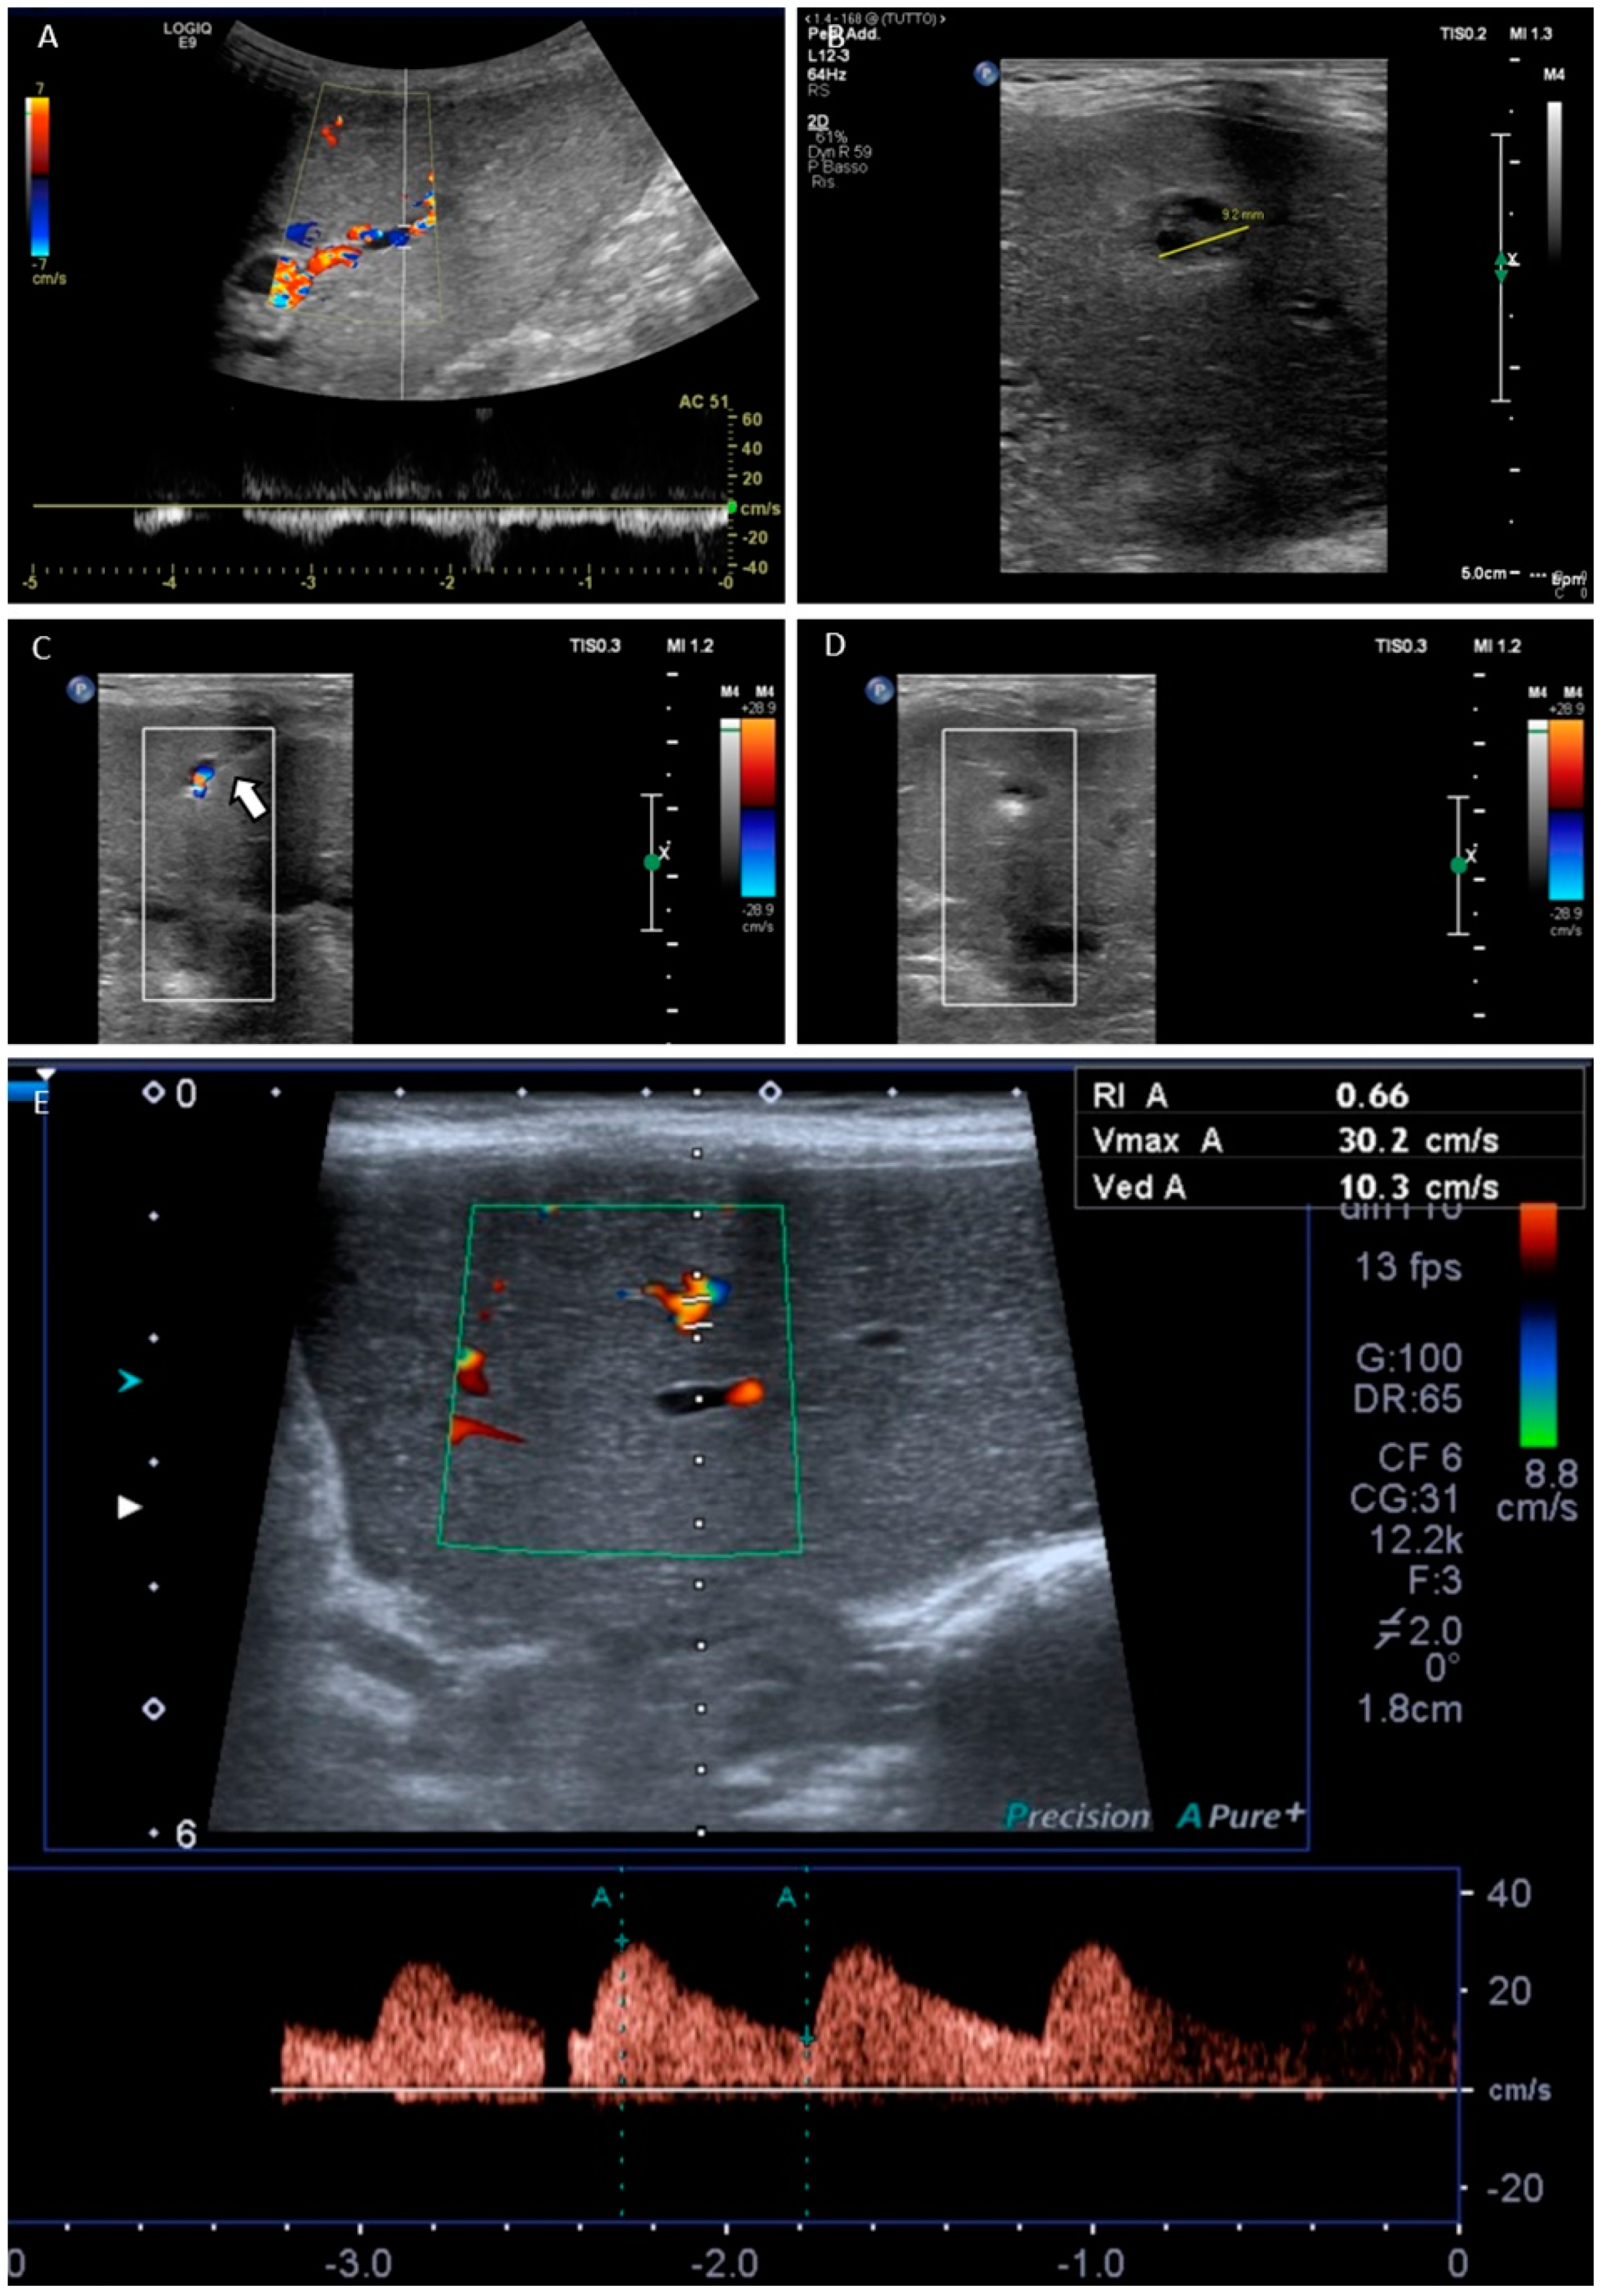

| 18 | endovascular | 7 | p-coils | none | 0.33 | n/a | yes | no | - | no | 0.66 | no | yes |